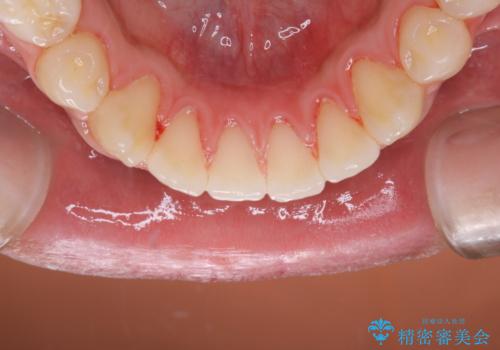

- 10年ぶりに歯科医院に来院された方です。クリーニングは人生で初めてとのことでした。

全体的に着色と汚れの量が多いため、PMTC60分コースで行いました。

歯石や着色、古くから蓄積した汚れは日常の歯ブラシではとることが出来ません。

歯科医院にて専門的に行うクリーニング(PMTC)を定期的に行うことがとても重要です。